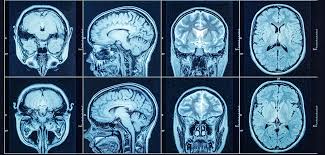

A CT (Computed Tomography) scan is a diagnostic imaging procedure that combines multiple X-ray images taken from different angles to create cross-sectional views of the body. These images provide detailed information about bones, blood vessels, and soft tissues, making it far more informative than a standard X-ray.

The machine rotates around the body, capturing images that a computer processes into slices. These slices help doctors diagnose conditions such as tumors, infections, fractures, and internal bleeding.

1. Head and Brain CT Scan

Used to detect strokes, tumors, or brain injuries.